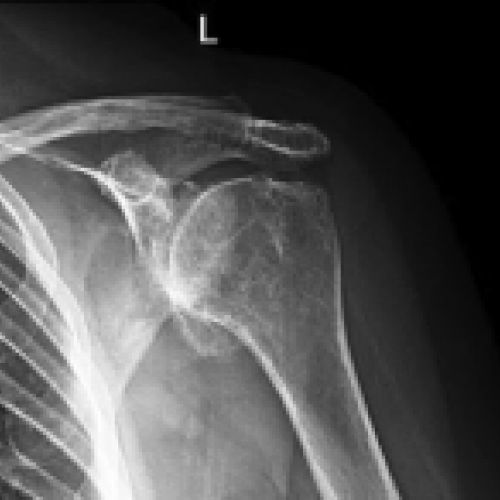

La articulación escapulohumeral es la que conecta la cabeza del húmero con la glena de la escápula, y es la articulación de la cintura escapular que mayor movimiento tiene, con desplazamiento en flexión y extensión del brazo, aproximación (aducción) y separación del mismo (abducción), rotaciones externa e interna, y movimientos combinados de antepulsión, retropulsión y circunducción. En esta articulación la artrosis se produce en la mayoría de los casos como consecuencia de traumatismos previos, inestabilidad o rigidez del hombro, artropatía por lesiones del manguito rotador, y osteonecrosis o enfermedades reumáticas que deforman la articulación.

Como consecuencia del desarrollo de artrosis escapulohumeral u omoartrosis, el paciente sufre dolor en el hombro y pérdida de movimiento del mismo. La cabeza humeral pierde su forma normal esférica y se va achatando, creciendo una corona osteofitaria en su periferia. Los tendones del hombro pueden estar afectados o no. Si el manguito rotador está roto la cabeza humeral asciende. La rotación externa está muy limitada y la abducción y antepulsión no suelen llegar a los 90º.